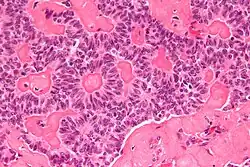

| Micrograph of a sex cord tumour with annular tubules. H&E stain. | |

It has a distinctive appearance under the microscope, from which it derives its name.

High magnification